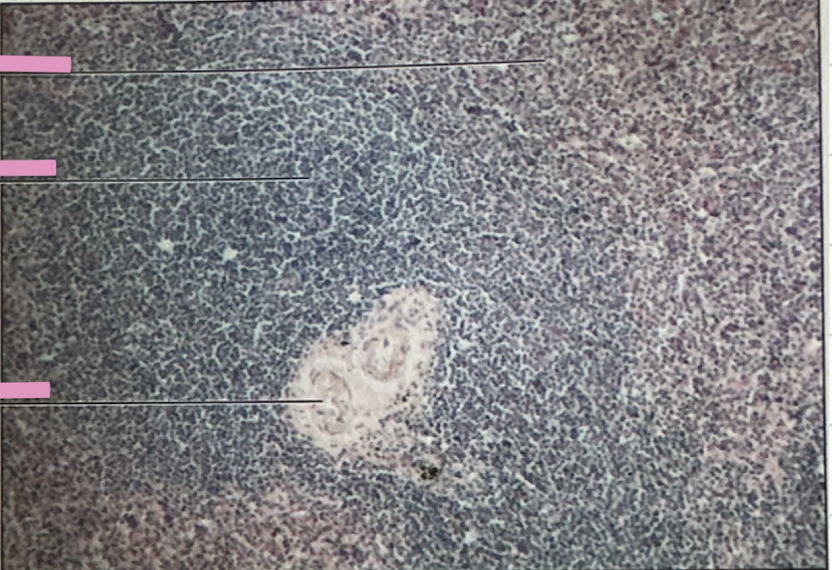

hodgkin’s granuloma

hodgkin’s granuloma

cancer of lymph system - breakdown of red and white pulp

reed-sternberg cells

derived from B lymphocytes